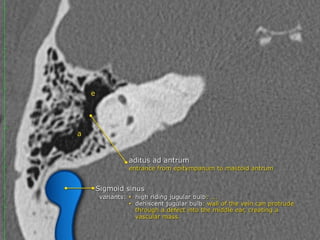

a) The Epitympanum :

• Communicates with the mastoid via the aditus ad antrum

• Normally, the mastoid is an air-filled cavity divided into

numerous compartments by mastoid septations

• The mastoid air-cell size and configuration are highly variable

• The mastoid air cells are traversed by the Koerner septum,

which is a thin bony structure formed by the petrosquamous

suture that extends posteriorly from the epitympanum,

separating the mastoid air cells into medial and lateral

compartments

• The medial mastoid air cells are separated from the adjacent

sigmoid sinus by the sigmoid plate

The tympanic cavity

 Medial wall

contains the oval and round window and the prominence of the

tympanic segment of the facial nerve.

 Lateral wall

is mainly formed by the tympanic membrane. The scutum is the bony

prominence at the upper part or pars flaccidum of the tympanic

membrane.

 Roof

is called the tegmen and separates the upper part of the tympanic

cavity or epitympanum from the middle cranial fossa.

 Posterior wall

forms the entrance to the mastoid and is called the aditus ad

antrum.